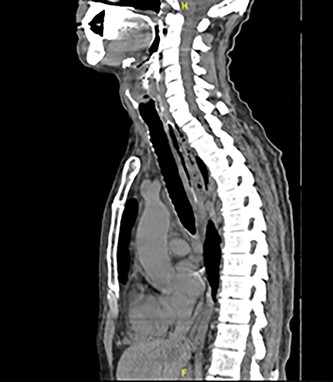

Full blood count, renal function and coagulation profile were within normal limits. C-Reactive protein was mildly raised at 73 mg/l. Neck axial contrast enhanced computer tomography (CT) scan was consistent with significant paraesophageal gas and mediastinitis (Fig. 1). Magnetic resonance imaging (MRI) suggested an enhancing collection from the left parapharyngeal space extending to the mediastinum (Fig. 2). Intravenous Fluconazole was added.

Axial plane MRI of neck and thorax showing a heterogenous collection on left parapharyngeal space extending inferiorly.